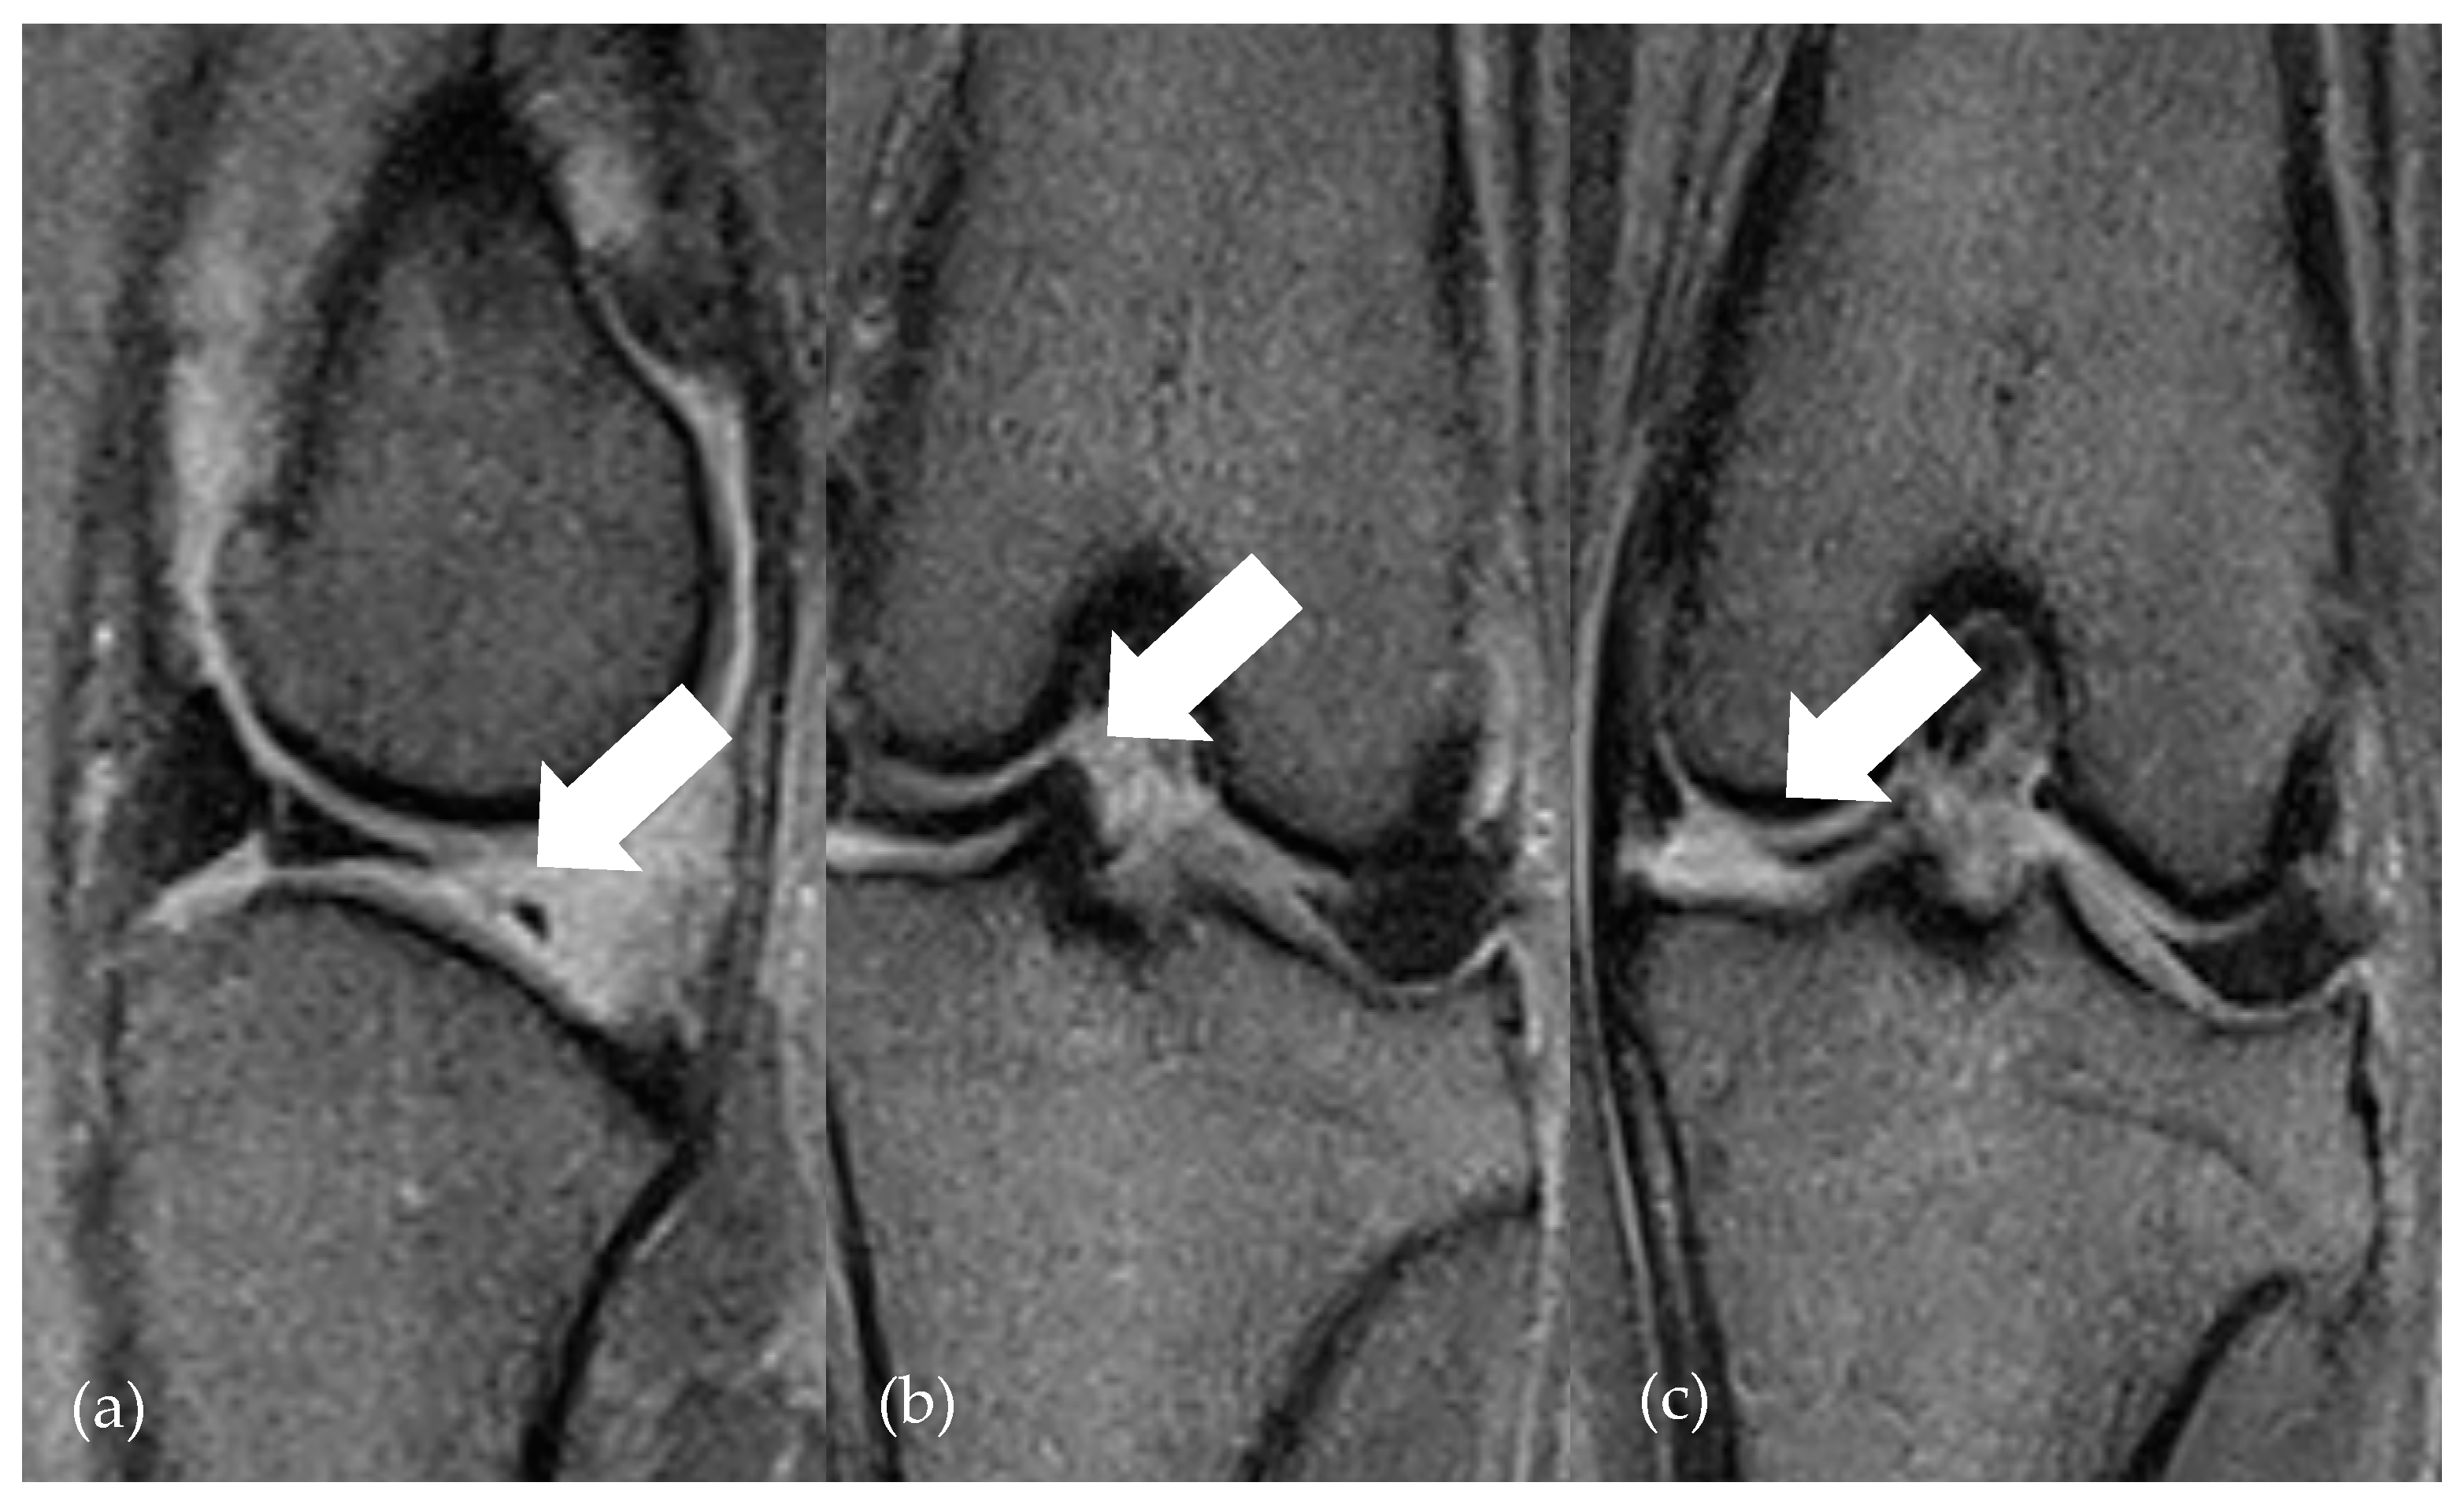

| Grade | Meniscal Pathology |

|---|---|

| 0 | without pathological findings |

| 1 | meniscus degeneration |

| 2 | mild axial fraying |

| 3 | severe axial fraying |

| 4 | not displaced rupture |

| 5 | bucket handle tear |

| 6 | folded medial meniscus |

| 7 | multiple dislocated parts of meniscus |